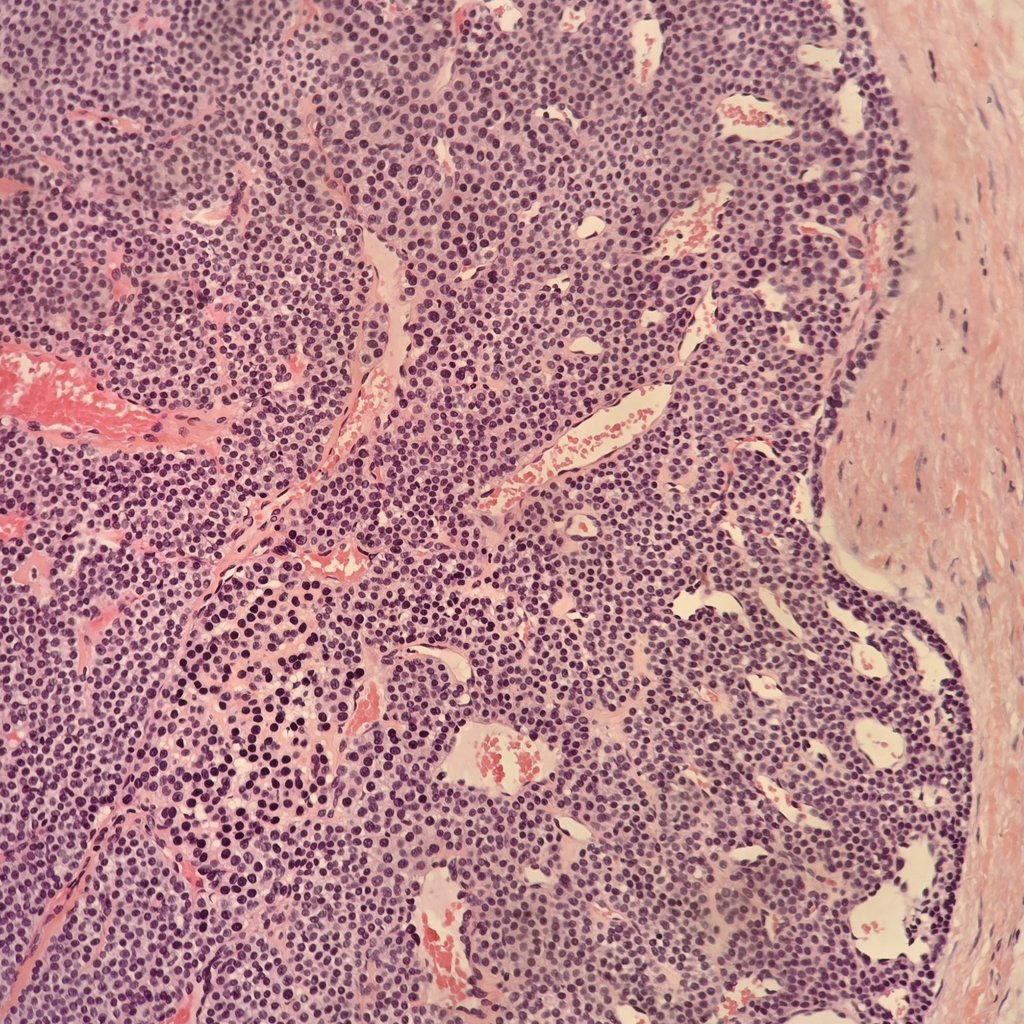

Two histological features of castleman disease : lollipop sign 🍭 (left) and onion skin appearance 🧅 (right) #xpath #pathology #PathTwitter